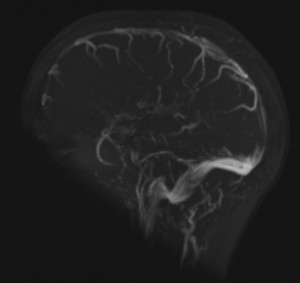

Cerebral veins

MRI showing cerebral veins